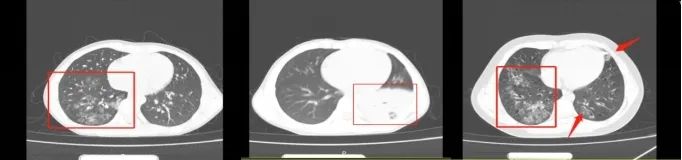

儿科医生表示:今年夏天,在浙江省立同德医院就诊的患儿中,支原体肺炎的患儿明显增加。病房中绝大部分患儿也都是支原体肺炎 ,与安安类似的情况也不在少数(见下图)。儿科病区满负荷运转,病房每天都是处于饱和状态。肺炎支原体感染一定要引起家长们的重视。